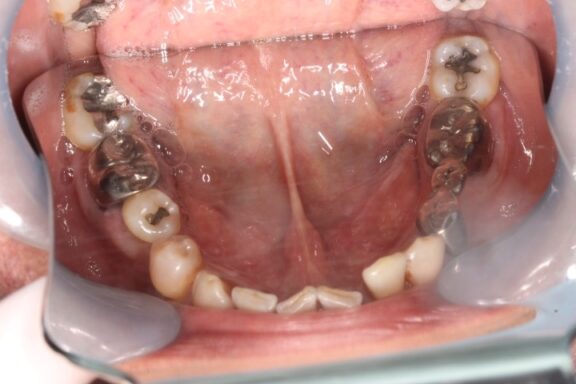

奥歯には複数の歯に銀を主成分とするメタル修復がされている状態でした。

今回は審美修復含めて、全体的に綺麗にしていく計画を患者様と一緒に建てさせていただきました。

今回は開口量、顎関節には全く問題なかったため、現在の顎位にて順番にジルコニア材料の被せ物にて治療を進めていきました。